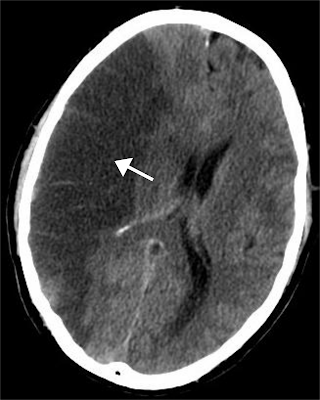

Acute hemorrhagic stroke, which is the least treatable form of stroke, affects more than 1 million people worldwide annually, with the outcome determined by the volume and growth of the underlying hematoma. Blood pressure often becomes elevated after intracerebral hemorrhage (ICH), frequently reaching very high levels, and is associated with poor outcomes.

- Elevated BP is very common in acute hemorrhagic stroke

- There is an association with elevated BP and:

- Increase in hematoma size

- Neuro-deterioration

- Dependency

- Death

In terms of guidance, the 2015 AHA guidelines are mainly based on the 2013 Interact 2 study. They recommend that for patients presenting with a systolic BP 150-220 that you aim for a systolic reduction to less than 140 and that this might be a reasonable option for patients who present with a BP > 220 as well.

In animal models of ICH and human imaging studies there is a zone of hypoperfusion surrounding a clot. So the questions is, will rapid reduction of BP in ICH result in infarction around the area of hemorrhage? There have been several studies which have looked at this question.